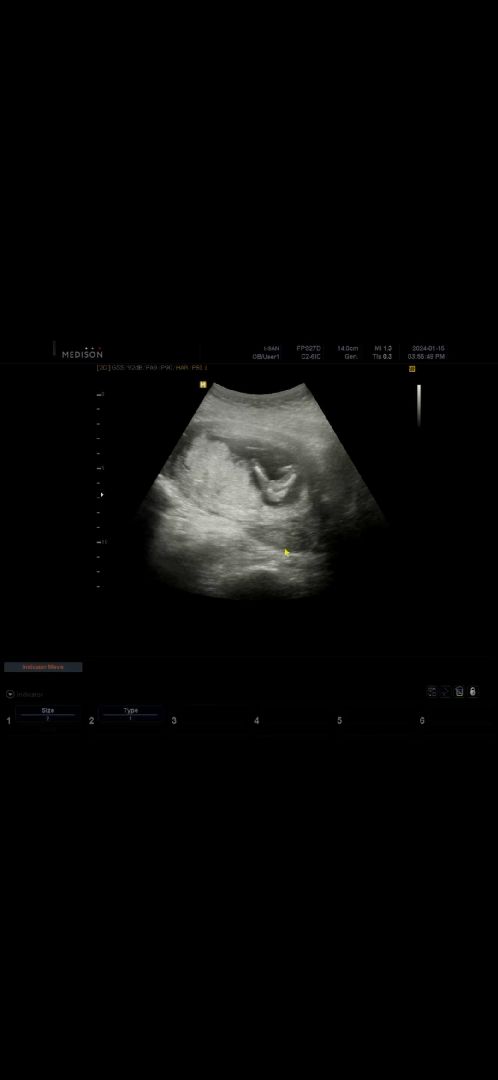

고수는 아니지만,, 저두 딸에 한표 던져봅니다🤣 어제 성별듣구왔는데 저희애기랑 똑같아보여요ㅋㅋ